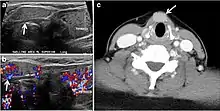

Fig. 8. A 48-year-old male patient post total thyroidectomy with PTC recurrence. a Transverse greyscale ultrasound of the neck demonstrates a left thyroid bed heterogeneous, predominantly hypoechoic irregular lesion with calcifications (white arrow). b A spot image of iodine 123 total body scan of the neck demonstrate a focus of abnormal radiotracer uptake at the left thyroid bed (Black arrows) between the annotated markers. c Enhanced axial CT scan of the neck demonstrates an enhancing large left thyroid bed mass (white arrow) with no calcifications. The lesion exerts a mass effect on the oesophagus (black arrow) and is inseparable from the trachea.[1]